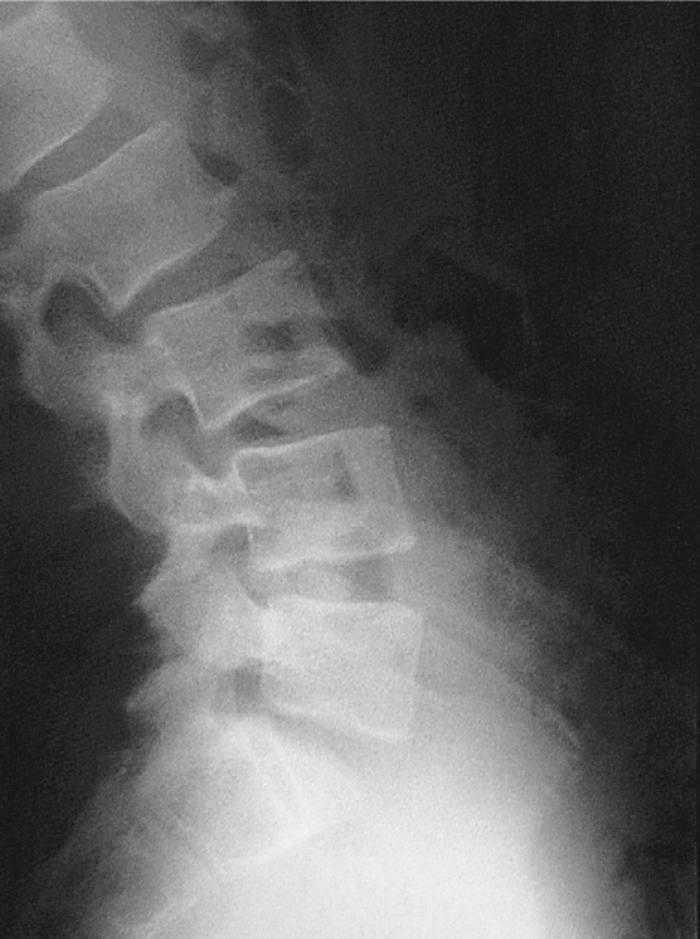

En la visita siguiente el paciente se presenta con radiografías que confirman el diagnóstico de espondilólisis L5 unilateral derecha (figs. 2 y 3). De acuerdo con el Documento de Consenso de la Societat Catalana de Medicina de l'Esport, se solicita una gammagrafía ósea planar (GOP) con tomografía computarizada por emisión de fotón simple (SPECT). Se decide continuar con el mismo tratamiento y se informa al paciente que será un tratamiento a largo plazo.

Figura 2

Figura 3